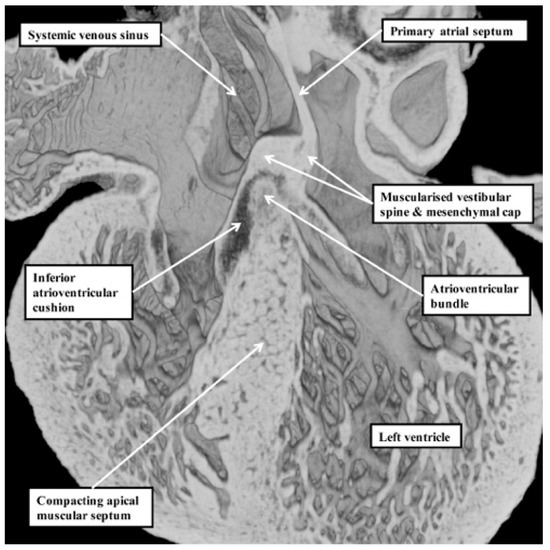

Our developmental findings are also pertinent to the suggestion that there is within the normal muscular ventricular septum a component derived from “the septum of the atrioventricular canal” [6]. It is now well established that such a septal component is, indeed, key to the separation of the initially common atrioventricular canal into the right and left atrioventricular junctions. This entity is the vestibular spine. Along with the mesenchymal cap carried on the leading edge of the primary atrial septum, the spine is muscularised to form the antero-inferior buttress of the atrial septum [8]. The spine was initially described in the 19th century [9], when it was called the “spina vestibuli”. Its importance was re-discovered by Snarr and colleagues, who described the entity as the dorsal mesenchymal protrusion [10]. Subsequent to the completion of septation, however, the myocardialised entities form part of the atrial, rather than the ventricular, septum. It is the location of the atrioventricular bundle, sandwiched between the crest of the muscular ventricular septum and the insulating tissues of the atrioventricular junctions, which confirms that in the normal heart, there is no ventricular “septum of the atrioventricular canal” (Figure 7) [11].

Figure 7. This image is a “four chamber” section through a dataset obtained from a developing mouse embryo at embryonic day 14.5. The location of the atrioventricular bundle, sandwiched between the crest of the muscular ventricular septum and the insulating tissues derived from the atrioventricular cushions, shows that there is no ventricular “septum of the atrioventricular canal” [8]. As can be seen, the structure responsible for dividing the initially common atrioventricular canal—the vestibular spine [9,10]—forms the antero-inferior buttress of the atrial septum.